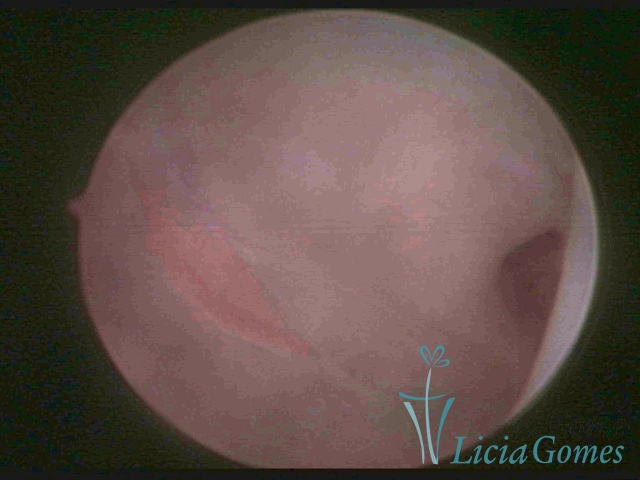

Bicornuate uterus

Malformation in which there is the lack of the flat portion of uterine fundus due to the lack of fusion on the proximal portion of paramesonephric ducts. The uterine fundus has two narrowed spaces in a divergent oblique angulation. It may be complete, from the fundus to the cervix; or partial, completely dividing the uterine cavity.

The tilted uterus which presents the most difficult hysteroscopic diagnosis occurs when there is only a small indentation of the uterine fundus.